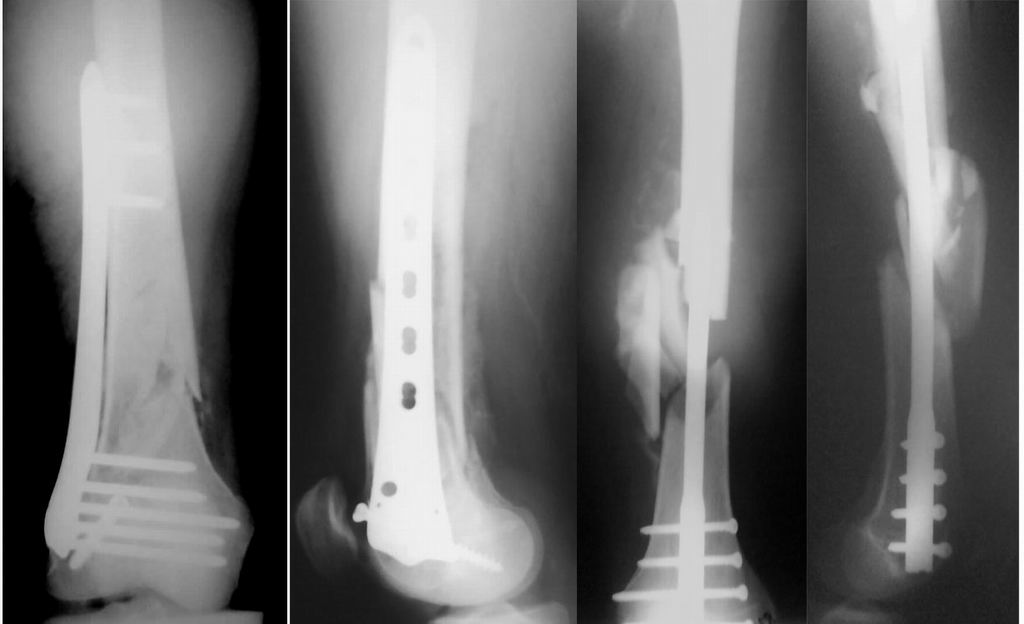

Мы бы не стали открывать, такие переломы срастаются, хотя бы и с краевым дефектом. То есть если удалять стержень потом, то сильно попозже обычного. В приложении пример. Сразу после операции и через 11 мес. Понятное дело, пациент к тому времени давно и не хромал, и функция колена была полная.

Уважаемые коллеги! От имени Алексея Смирнова всем спасибо за обсуждение. Больной прооперирован. Снимки в приложении.